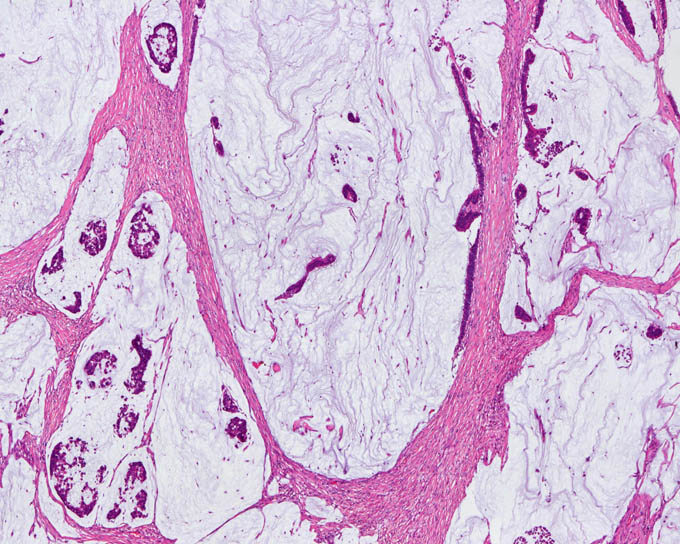

病理標本 大腸 粘液癌 分化型 新潟大学医学部臨床病理学分野い

壁外発育型大腸粘液癌の1例 臨床雑誌外科 67巻10号 医書 Jp